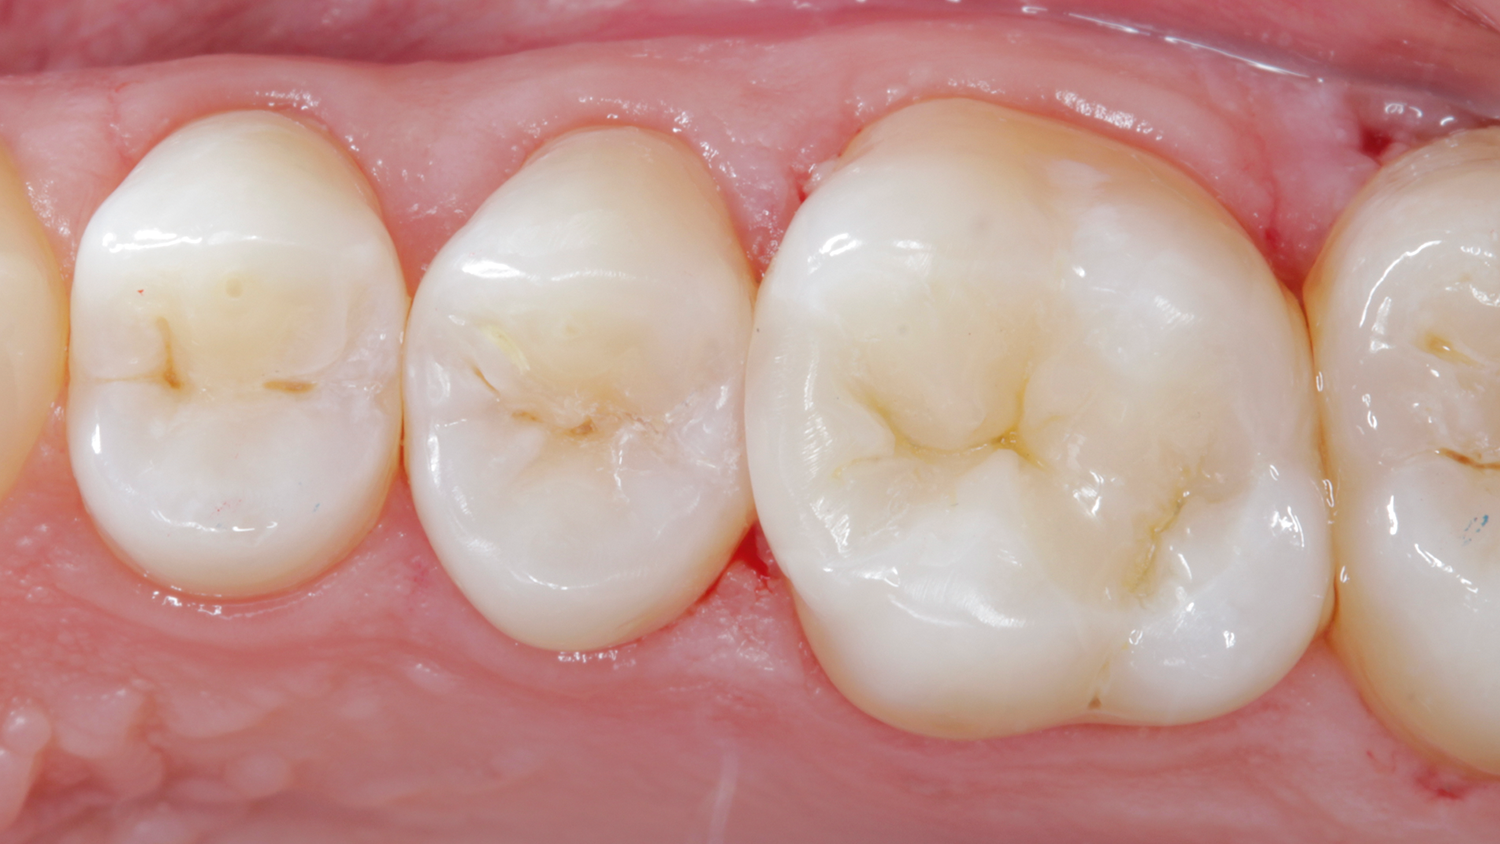

Case: In cases where the gingival fl oor of the proximal box is subgingival, a marginal elevation procedure may be accomplished with SDR flow+ base material. After marginal elevation, rubber dam is applied and a class II restoration is placed with a class II solution technique.

Results: Radiographic control, notice excellent marginal adaptation, seamless transition from SDR flow+ bulk fill material to Ceram.x Spectra ST composite material and lack of air-bubble entrapment.